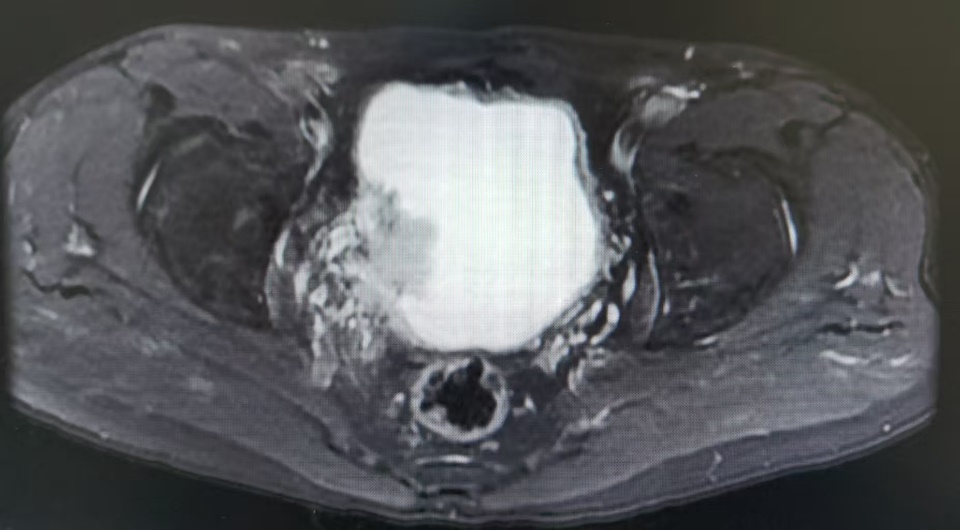

教授团队近期完成的一例高难度保膀胱手术,为这类患者带来了新的希望。肿瘤不仅侵犯膀胱肌层,更累及右侧输尿管壁内段,传统上几乎必然选择根治性切除。但患者保膀胱意愿强烈,影像学提示为局限性MIBC,团队决定迎难而上,开展经尿道保膀胱手术。医脉通特邀孙圣坤教授,为我们深入解析该病例的全过程,并展示关键手术视频,以飨读者。

肿瘤不仅侵犯膀胱肌层,更累及了右侧输尿管壁内段。传统的处理方式是行膀胱根治性切除术。但患者保膀胱意愿强烈,MRI检查提示为局限性MIBC,试行经尿道保膀胱手术。